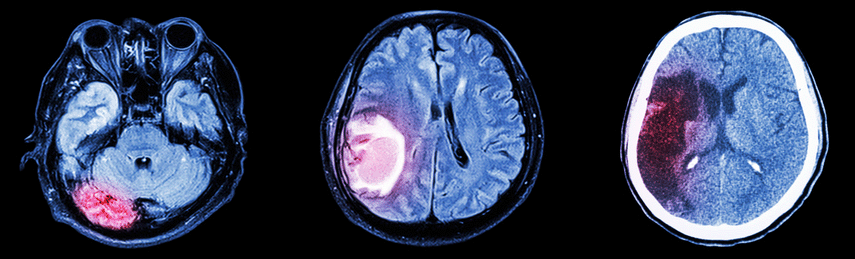

Simply put, a stroke is a "brain attack." It occurs when part of the body loses function due to a disruption of blood flow in the brain. When this happens, either because of blockage from buildup in the arteries or when a vessel in the brain bursts, the affected area can’t get oxygen or nutrients. This can cause a wide range of symptoms, including the following:

Ischemic stroke is the most common type of stroke. This type of stroke can result from clogged or damaged arteries, such as in atherosclerosis or arterial dissection or blood clots that travel to the brain from other areas of the body. A clot that forms in clogged arteries in the brain is called a cerebral thrombus. A clot that breaks loose and moves through the blood to the brain is called a cerebral embolism.

Hemorrhagic stroke is a very serious form of stroke that refers to spontaneous rupture of an artery in the brain. The resulting increase in pressure, and irritating effect of blood on the brain tissue, can lead to neurologic deficits similar to an Ischemic Stroke.